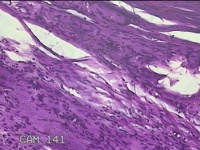

左示指肿物

性别

男

年龄

35岁

临床诊断

左示指末节肿物性质待查?

一般病史

发现左示指肿物

标本名称

大体所见

灰白暗红色肿物0.7x0.3x0.2cm一个,表面糜烂,切面灰白暗红色,质软。